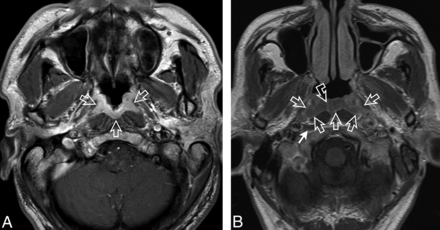

NPC involved the adenoid in 111 patients and/or the walls in 183 patients. Affected subsites, including those deep to the adenoid, were the lateral nasopharyngeal recess, the roof, and the posterior/inferior subsites in 157/189 (83.1%), 184/189 (97.4%), and 148/189 patients (78.3%), respectively. Twenty of 189 patients (10.6%) had 1 subsite only, and all subsites were affected bilaterally in 12/189 patients (6.3%). The tumor center was lateral in 134/189 patients (70.9%) (Fig 1), of which 95 crossed the midline; central in 25/189 patients (13.2%) (Fig 2); and diffuse in 30/189 patients (15.9%) (Fig 3). NPCs were enhanced heterogeneously in 129/189 patients (68.3%) (Fig 1C). Despite large variations in size, asymmetry, and signal intensity between the 2 halves of the nasopharynx, almost all cases exhibited the deep mucosal white line (180/183, 98.4%) (Figs 1A, -B and 3B), which was interrupted in at least 1 slice in 153/180 patients (85%) (Fig 1B). Furthermore, the adenoidal septa were absent/distorted in 111/111 patients (100%) with an adenoid (Fig 2). Further details are presented in the On-line Table.

A, Axial T1-weighted postcontrast MR image of the nasopharynx in a 51-year-old man with NPC (open arrows). A symmetric tumor with diffuse involvement of all nasopharyngeal walls exhibits homogeneous contrast enhancement without a white line along the deep mucosal margin. B, Axial T1-weighted postcontrast MR image of the nasopharynx in a 59-year-old man with NPC (open arrows). A symmetric tumor with diffuse involvement of the nasopharyngeal walls exhibits homogeneous low contrast enhancement and an intact mucosal white line along the deep margin. The adenoid extends along the posterior wall from the roof, with an adenoidal “stripe” on the right (curved open arrow) but not on the left side. A small right retropharyngeal node is also indicated (solid arrow). The patient had bulky N3-stage metastatic nodes below this level.